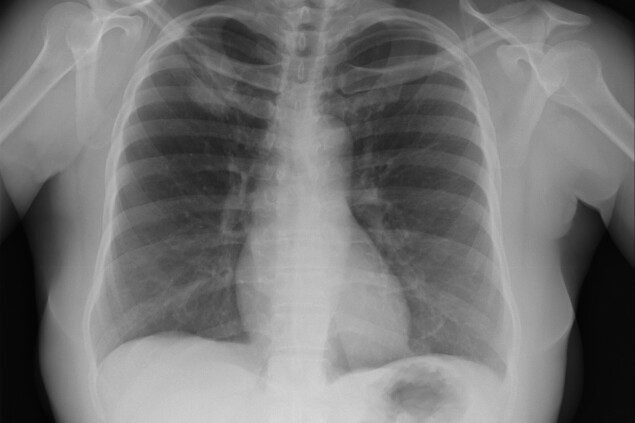

В 2022 году в мире от рака умерли 9,7 миллиона человек. У каждого пятого был рак легких, что делает его самым распространенным видом онкологических заболеваний. Россия занимает пятое место в топе стран, где его чаще всего диагностируют. За 2022 год рак легких забрал жизни 51 тысячи россиян.

У некурящих пациентов (как и у курильщиков) наиболее распространена аденокарцинома — около 50–60% случаев. Этот тип рака легких развивается в клетках эпителия, которые вырабатывают слизь. Еще около 10–20% случаев связаны с плоскоклеточными карциномами, которые развиваются во внутренних слоях легких. Остальное — это мелкоклеточный рак и более редкие типы болезни.

Симптомы рака легких одинаковы у всех — неважно, курит человек или нет. В основном они проявляются в дыхательных путях: кашель (иногда с кровью), одышка, боль в груди и хрипы, а также беспричинная усталость и потеря веса. У большинства людей симптомы появляются только на поздней стадии болезни.

«Если где-то в ваших легких спрятана опухоль размером один сантиметр, вы ее не заметите», — предупреждает онколог из Университетской больницы Цюриха Андреас Вики